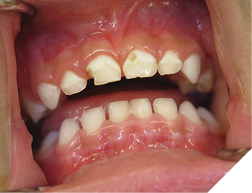

Early Childhood Caries (ECC) or Baby Bottle Syndrome (BBS) is a rampant form of tooth decay that destroys the newly erupted primary teeth very quickly. The tooth decay progresses at an astonishingly quick rate and will occur even before the tooth fully erupts. ECC is different from normally occurring tooth decay in that it appears at a very early age, usually before the age of 2, and involves mostly the maxillary incisors. In later stages it can involve upper first maxillary molars and the lower molars as well if the child is still bottle feeding after two-and-a-half years of age. The mandibular incisors are rarely involved. The decay progresses very rapidly and can destroy the whole erupted tooth in a number of months (Fig. 1). Typical forms of caries are usually not as aggressive and usually start in the pits and fissures or interproximally on the molars. Typical dental caries do not usually occur at a very early age, for example below the age of 2 years.

Fig. 1

ECC occurs in young children who are fed nocturnally on demand with a fermentable carbohydrate, typically milk. Night-time feeding, whether by bottle or breast feeding, before the eruption of the maxillary incisors is not problematic. Taking a baby bottle during the day, no matter how frequently, does not seem to cause this problem. Feeding a child with a baby bottle before going to sleep is also not problematic. This may be due to the self-cleaning action of the salivary flow during the daytime. With EEC there is reduced salivary flow at night, so the substates are not washed away, but stay on the surface of the teeth. The substances in the bottle also have an effect. The more carbohydrates, the more virulent the decay. A sweetened drink such as apple juice is worse than milk, which is worse than natural breast milk. The substate stays on the tooth surface all night and is replenished regularly by repeated feedings. Why are the maxillary incisors so severely decayed, while the mandibular incisors are virtually immune with ECC? The mandibular incisors are largely unaffected due to the position of the child’s tongue while feeding. As the child sucks on the bottle, the tongue covers and protects the mandibular incisors. The primary incisors when newly erupted are not yet fully calcified and may explain why the decay progresses so quickly. The maxillary first molars may be involved but the maxillary cuspids are usually not involved as they erupt later. The second molars of both jaws may be involved if the child is still night feeding after they erupt. It may be difficult to determine if the teeth are painful, especially if the child is colicky. A good sign that the teeth are painful is that the child is not biting with their front teeth, and yet they have no other teeth. You should note that if the decay of the teeth is extensive and the teeth are infected, with draining fistulas, there may not be any pain (Fig. 1). The treatment depends at what stage you catch the disease. In the very early stages, before cavitation or incipient lesion stages, you can institute preventive measures, such as good oral hygiene with a fluoridated toothpaste and regular topical fluoride applications. However, for these recommendations to work, the night feeding must stop. Incipient lesions will appear as white frosty areas of decalcification lesions on the buccal surfaces of the teeth (Fig. 2).